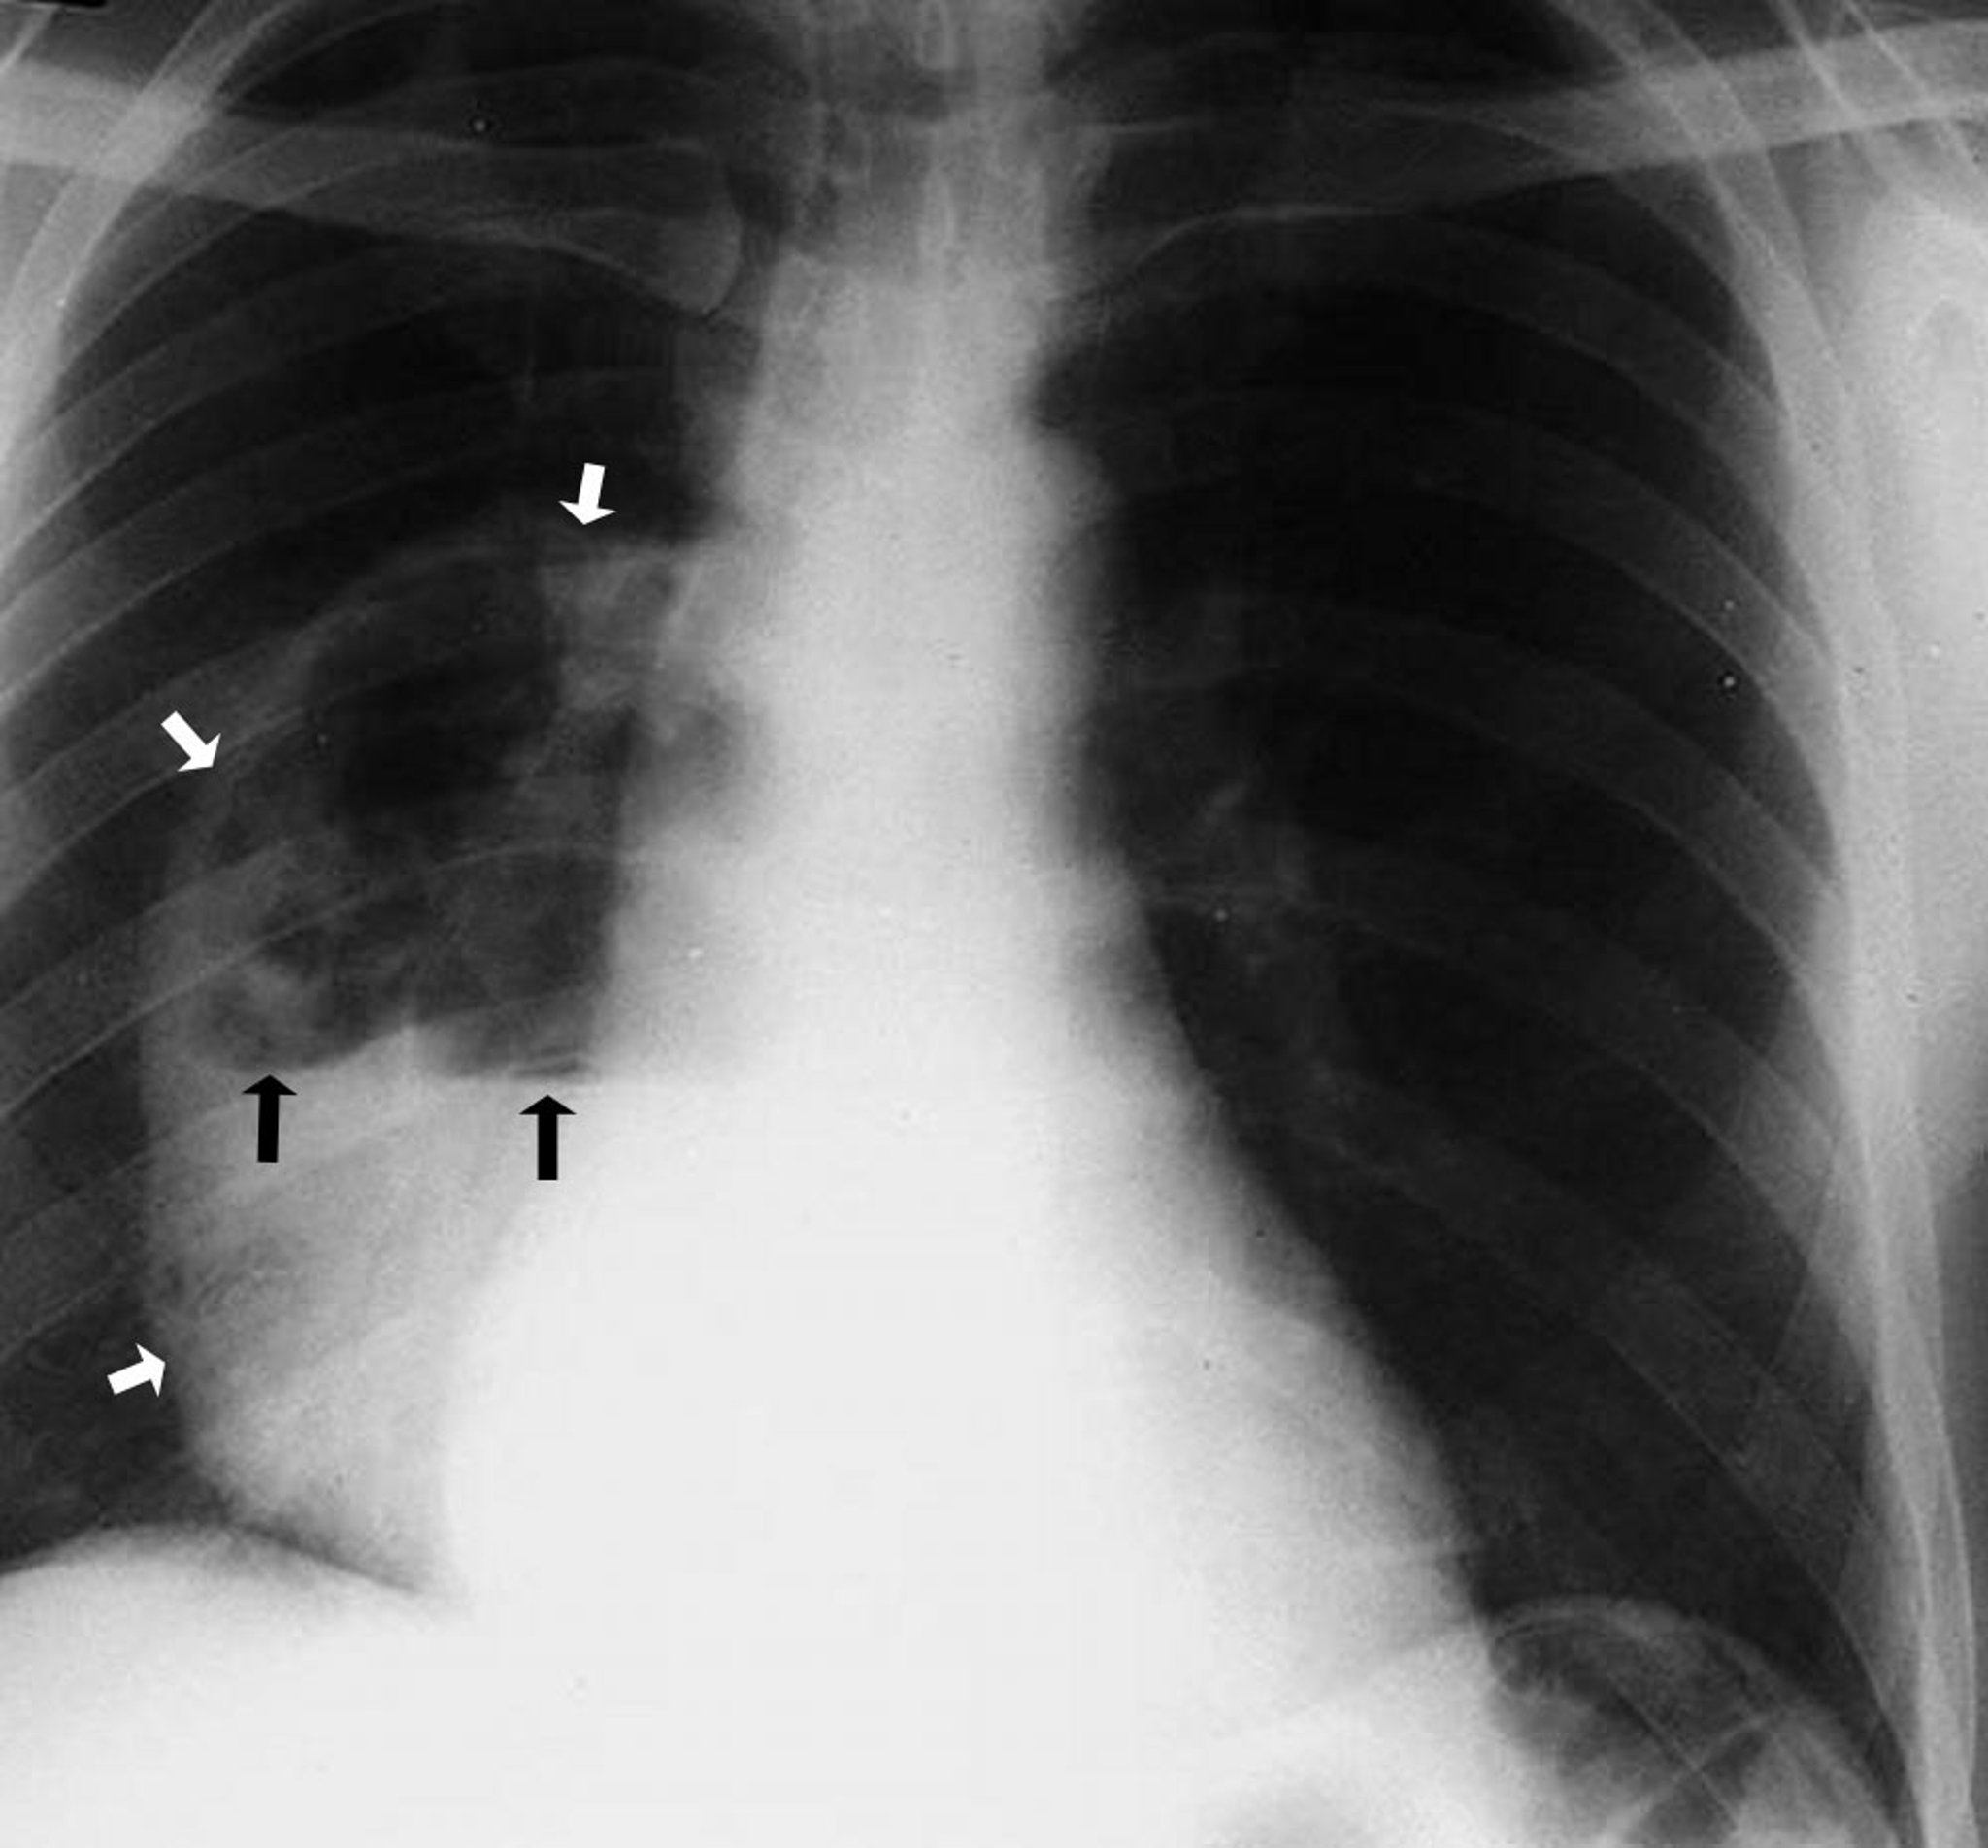

Abcès pulmonaire (radiographie)

Cette photo montre un grand abcès du lobe inférieur droit montrant une cavité qui contient un niveau hydro-aérique. Les flèches blanches pointent la limite de l’abcès, montrant les parois séparées du parenchyme pulmonaire. Les flèches noires délimitent le niveau où l’air au-dessus et le liquide en dessous se rencontrent.

By permission of the publisher. D'après Leaf H. In Atlas of Infectious Diseases: Pleuropulmonary and Bronchial Infections. Edited by GL Mandell (series editor) and MS Simberkoff. Philadelphia, Current Medicine, 1996.